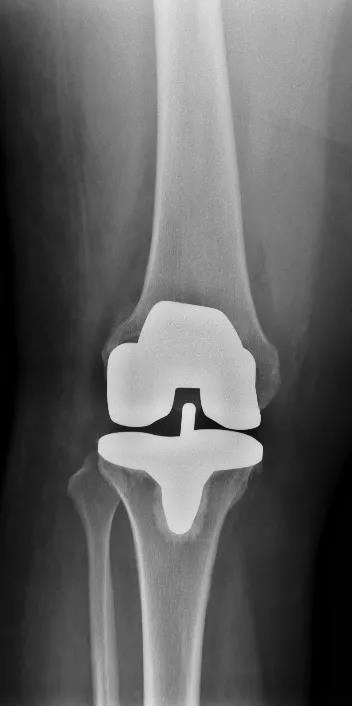

因施女士有冠心病支架植入病史,术前通过心内科、麻醉科多学科会诊后,决定一期行右全膝关节置换术,二期再行左侧膝关节置换手术治疗。8月4日,在张金山副院长的带领下,为施女士顺利地进行了右侧人工全膝关节置换术,手术效果十分显著。

我院张金山副院长表示,“医用耗材带量集中采购,以量换价”让患者住院费用得到了大幅度的降低,以施女士实行的膝关节置换手术为例,手术耗材较以往降价1万多元,全部住院费用通过农保报销后患者仅需自费1万多元,此政策利国惠民,保障医疗质量不变的同时大大解决患者的经济难题,保证了我市人民的健康,也是落实健康中国战略的重要举措。